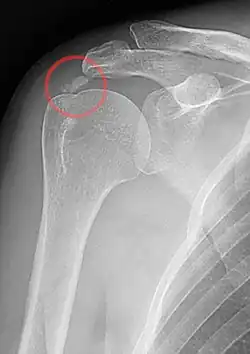

| A plain X ray of the shoulder showing calcific tendinitis | |

Calcific tendinitis is a common condition where deposits of calcium phosphate form in a tendon, sometimes causing pain at the affected site. Deposits can occur in several places in the body, but are by far most common in the rotator cuff of the shoulder. Around 80% of those with deposits experience symptoms, typically chronic pain during certain shoulder movements, or sharp acute pain that worsens at night. Calcific tendinitis is typically diagnosed by physical exam and X-ray imaging. The disease often resolves completely on its own, but is typically treated with non-steroidal anti-inflammatory drugs to relieve pain, rest and physical therapy to promote healing, and in some cases various procedures to breakdown and/or remove the calcium deposits.

Calcific tendinitis is typically diagnosed by physical examination and X-ray imaging.[1] During the formative phase, X-ray images typically reveal calcium deposits with uniform density and a clear margin.[1] In the more painful resorptive phase, deposits instead appear cloudy and with unclear margins.[1] By arthroscopy, formative stage deposits appear crystalline and chalk-like, while resorptive stage deposits appear smooth resembling toothpaste.[1] Ultrasound is also used to locate and assess calcium deposits. In the formative stage, deposits are hyperechoic and arc-shaped; in the resorptive stage deposits are less echogenic and appear fragmented.[1][3]